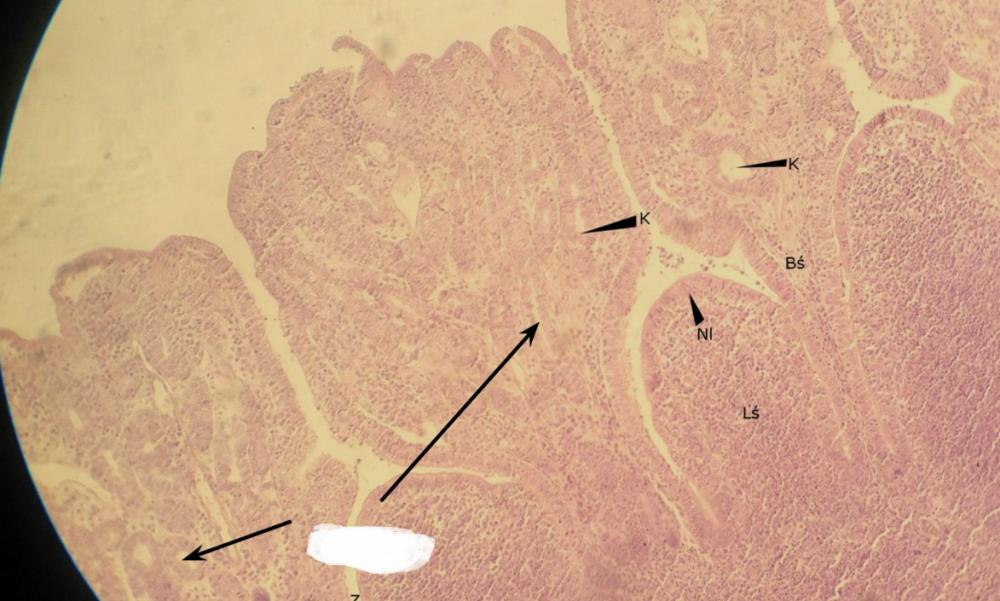

Pytanie 437

grudka chłonna (wyrostek robaczkowy)

Pytanie 438

zatoka limfatyczna (wyrostek robaczkowy)

Pytanie 439

błona śluzowa (wyrostek robaczkowy)